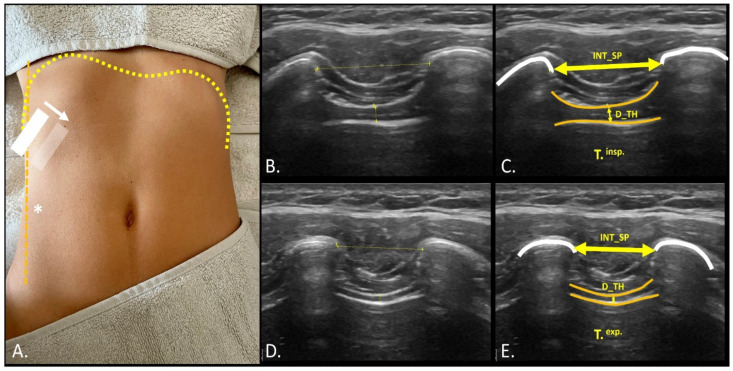

Methods: An observational, cross-sectional study was conducted with 44 female participants (22 with PD and 22 healthy controls). Diaphragmatic structure was evaluated through ultrasound, measuring the intercostal distance, diaphragmatic thickness, and diaphragmatic excursion at rest and during maximum voluntary contraction. Spirometric assessments included forced vital capacity (FVC), forced expiratory volume in the first second (FEV1), and the FVC/FEV1 ratio, along with measurements of maximum inspiratory pressure (MIP) and maximum expiratory pressure (MEP). Group differences were analyzed using Student's t-test and effect sizes were reported with Cohen's d.

Results: No significant differences were observed between the groups in diaphragmatic thickness, diaphragmatic excursion, or global respiratory capacity (p > 0.05). However, women with PD presented a significant reduction in the left intercostal distance both at rest (p = 0.035, d = 0.56) and during contraction (p = 0.039, d = 0.54). No other significant group differences were detected.